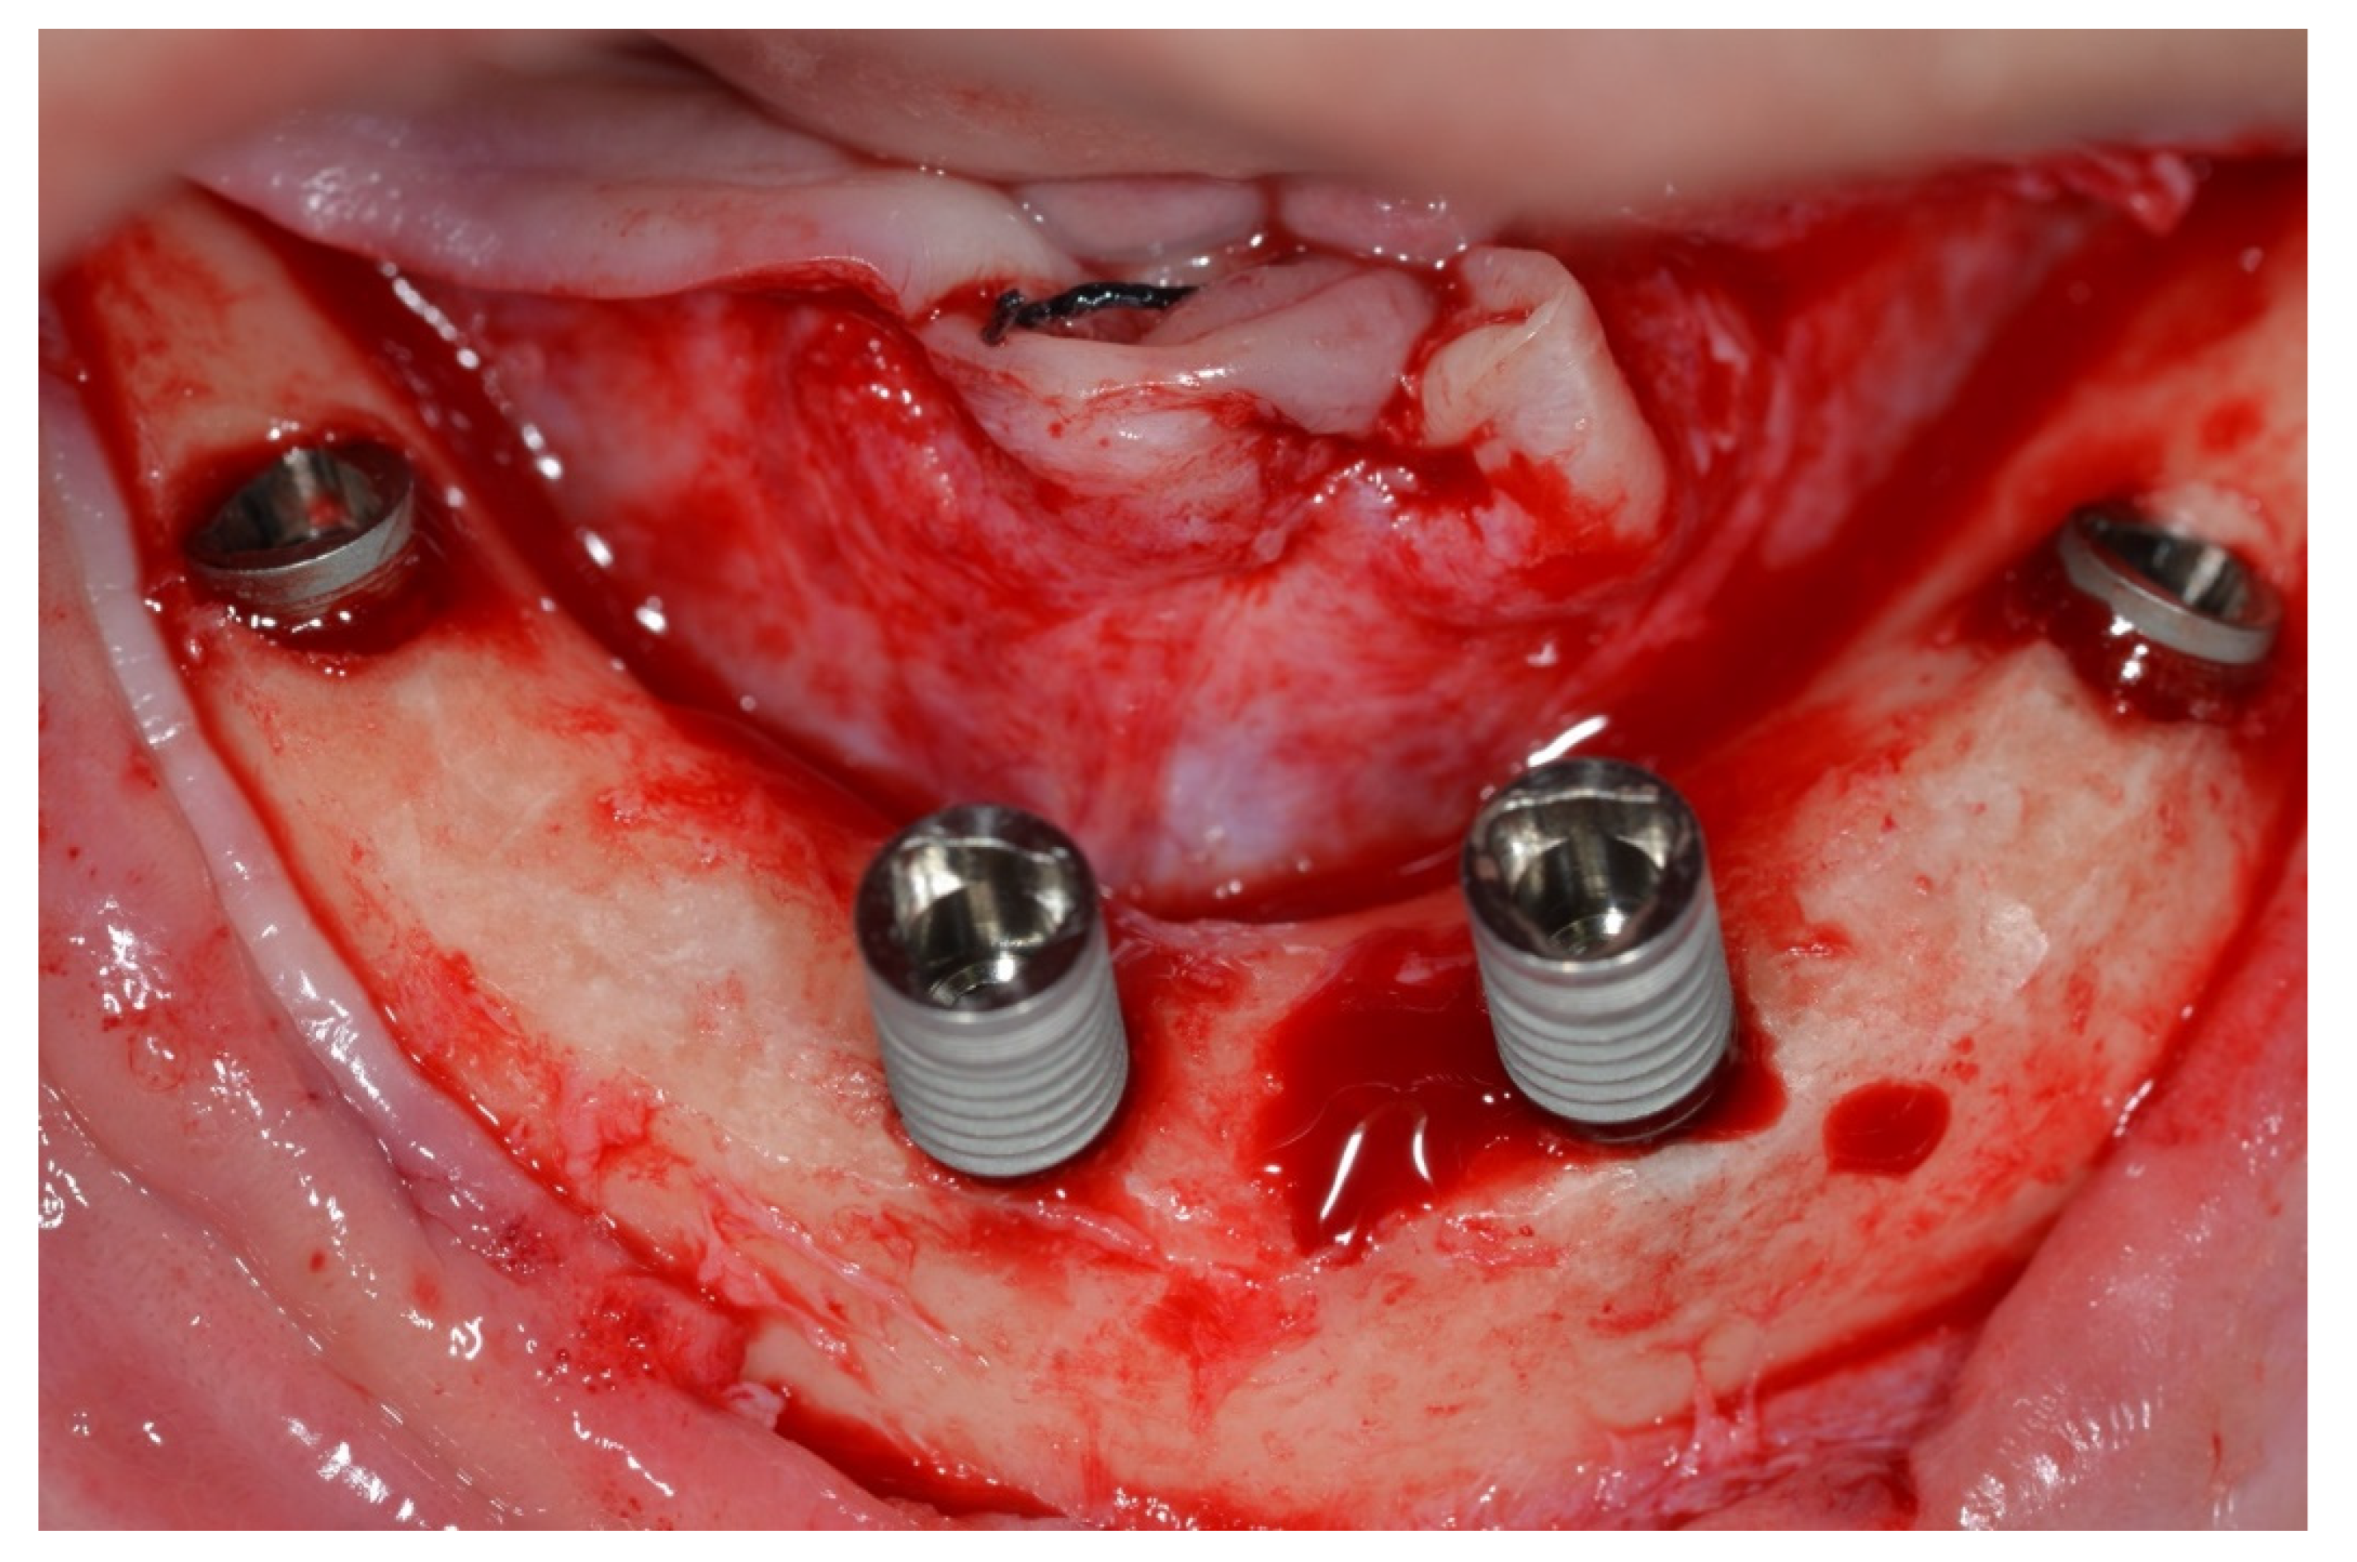

Surgical Protocol